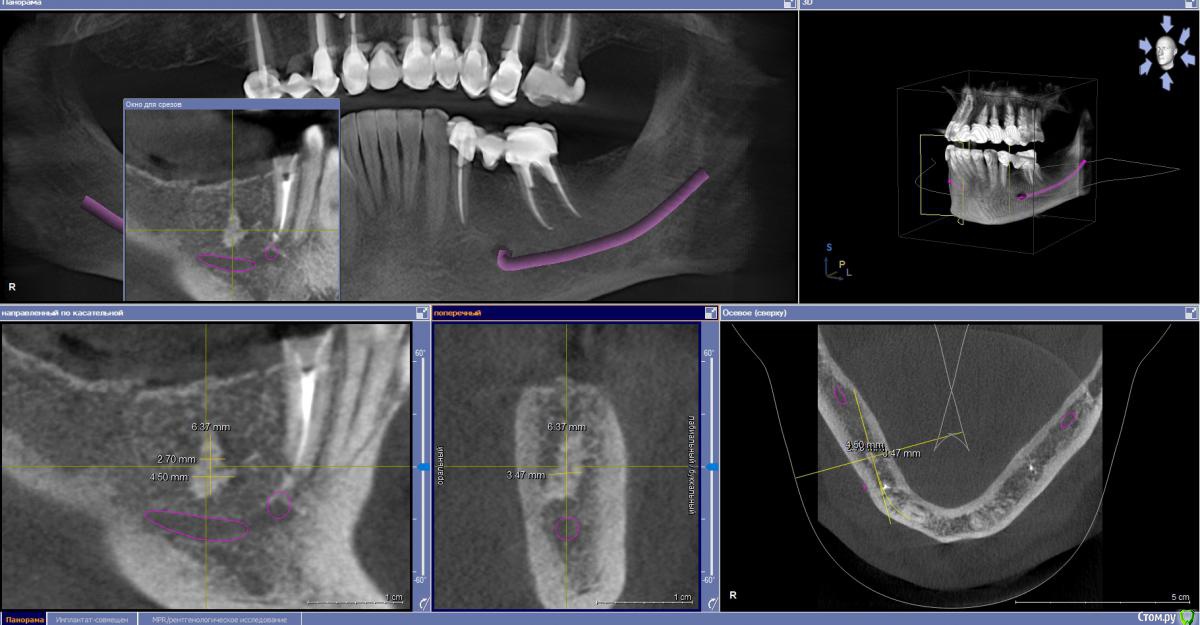

zumanok Опубликовано 21 мая, 2019 Поделиться Опубликовано 21 мая, 2019 Здравствуйте доктора.При планировании имплантации обнаружилось образование по плотности похоже на кортикальную кость, Обойти ее получается только при удалении соседнего корня и имплантации в 4.5- 4.7, хотя его можно восстановить. Как вы действуете в таких случаях или какое мнение? Есть ли подобный опыт? Ссылка на комментарий

krokomot Опубликовано 22 мая, 2019 Поделиться Опубликовано 22 мая, 2019 Это не одонтома, то что вы описываете больше походит на остеому или участок гиперостоза, и то и то не противопоказано при имплантации, в отличие от одонтомы. 2 Ссылка на комментарий